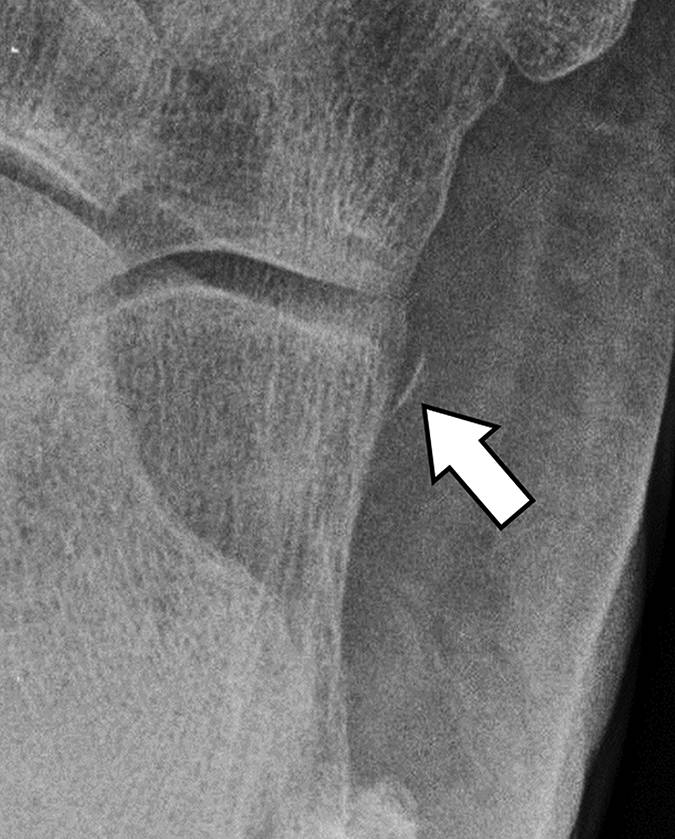

图6A-侧位片显示了通过从内侧足底发出的内皮断裂(直箭头)。注意(曲线箭头)跟骨下部方面的碟状缺陷。